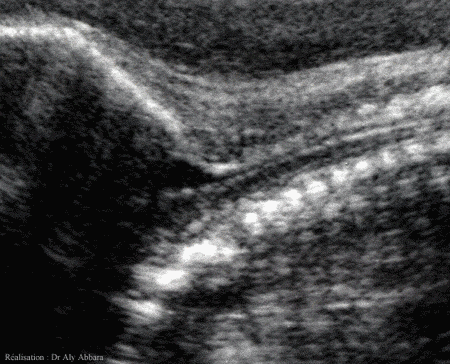

Coupe sagittale cervico-cérébrale montrant

le canal rachidien et la moelle épinière

Fœtus de 33 SA